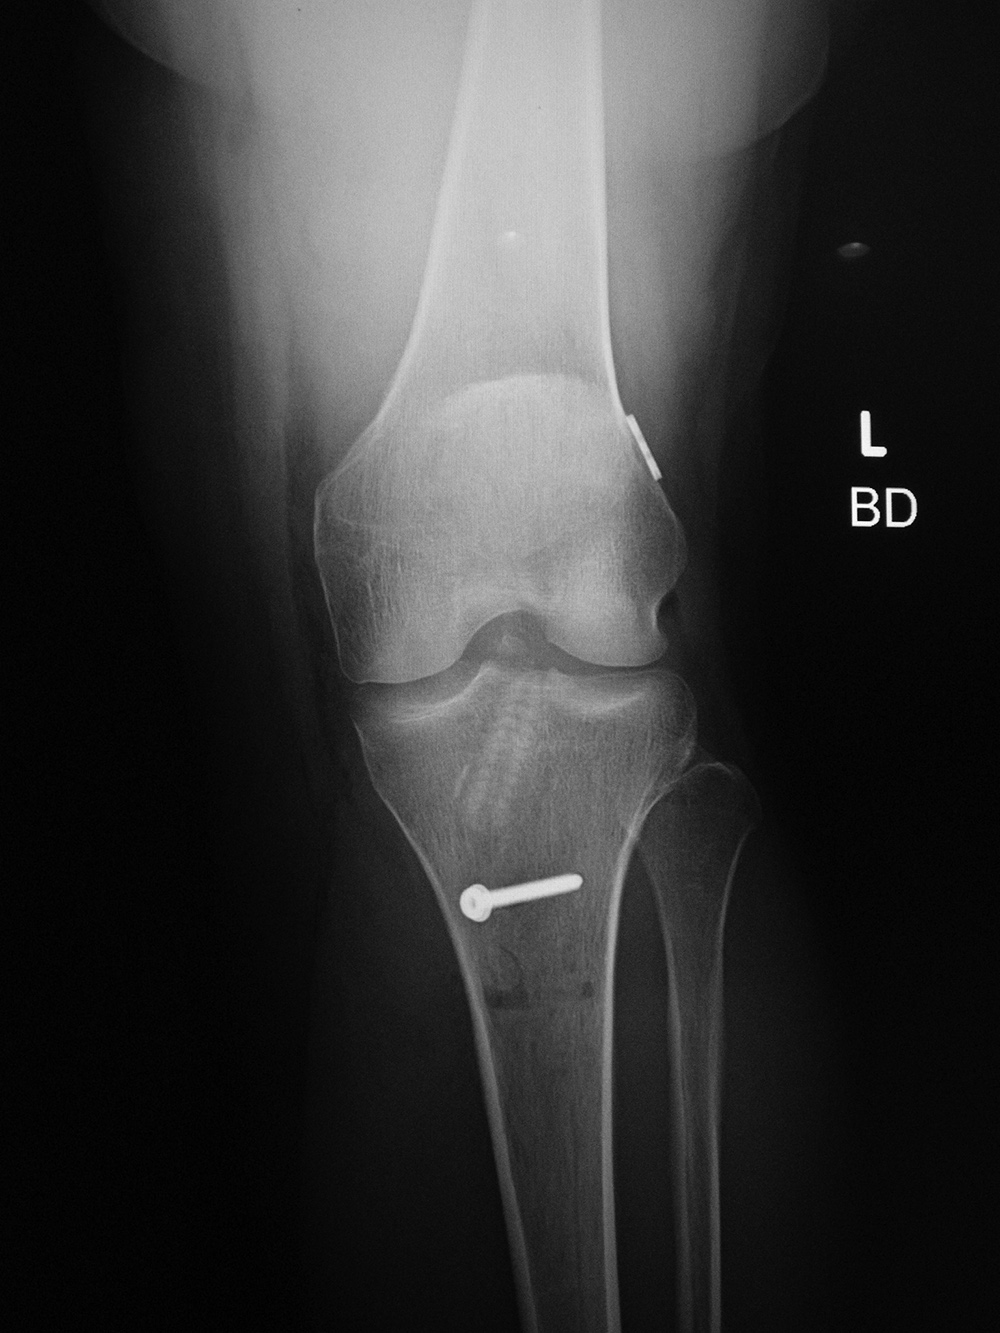

Buttress plates are used more for bony alignment rather than compression. They are indicated for situations in which the fracture fragments are unstable in compression or axial loading. They are most commonly found in the distal radius and in the proximal tibia where they stabilize tibial plateau fractures (figure: buttress plate with bone substitute; figure tibia buttress plate). They are also sometimes found in distal femur intercondylar fractures (figure: femur buttress plate).

Medial open wedge high tibial osteotomy is a well-established procedure for the treatment of medial knee joint osteoarthritis and symptomatic varus malalignment. Puddu or TomoFix plates systems are specifically designed for use with osteotomies close to the knee, particularly the high tibial osteotomies for treatment of medial compartment knee arthritis or sometimes for opening wedge distal femoral varus osteotomies for treatment of lateral compartment knee arthritis (Puddu, 2007) (figure: tibial osteotomy plate; figure: Puddu titanium plate with hydroxyapatite bone graft wedge).